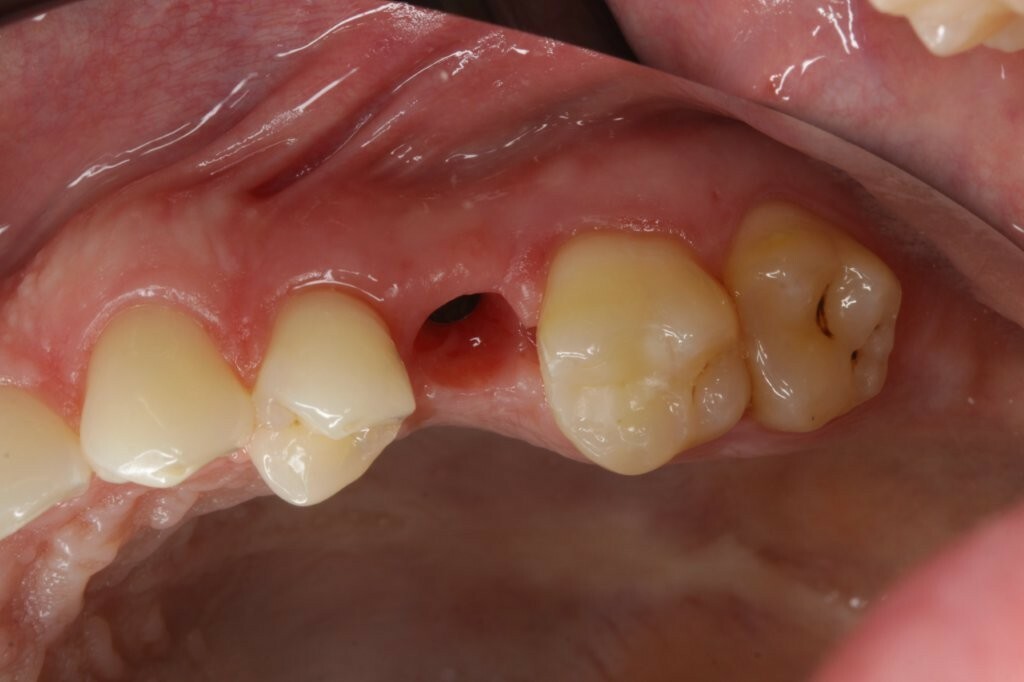

Ein Patient mit einem gepflegten Gebiss in eugnather Verzahnung (Abb. 1) stellte sich aufgrund einer Kronen-Wurzelfraktur an Zahn 25 in der Praxis vor. Die Untersuchung ergab, dass der Zahn aufgrund einer Fraktur des palatinalen Höckers mit subkrestalem Frakturverlauf (Abb. 2) nicht erhaltungswürdig war.

Nach der Zahnextraktion wurden dem Patienten mehrere Therapieoptionen vorgestellt. Er entschied sich für ein Titanimplantat, auf dem eine vollkeramische Krone aus Lithiumdisilikat (IPS e.max CAD, Ivoclar Vivadent) befestigt werden sollte.

Zu Beginn wurde das Einzelzahnimplantat (Conelog ScrewLine Titanimplantat, 3,8 x 9,0 mm, Camlog) in Regio 25 gesetzt, geschlossen eingeheilt und nach Freilegung mit einem Gingivaformer (Conelog Gingivaformer, wide body, 3,8 x 6,0 mm, Camlog) versehen (Abb. 3). Mithilfe eines VITA-Farbschlüssels (VITA Zahnfabrik) wurde für die spätere Krone die Farbe A3 bestimmt (Abb. 4).